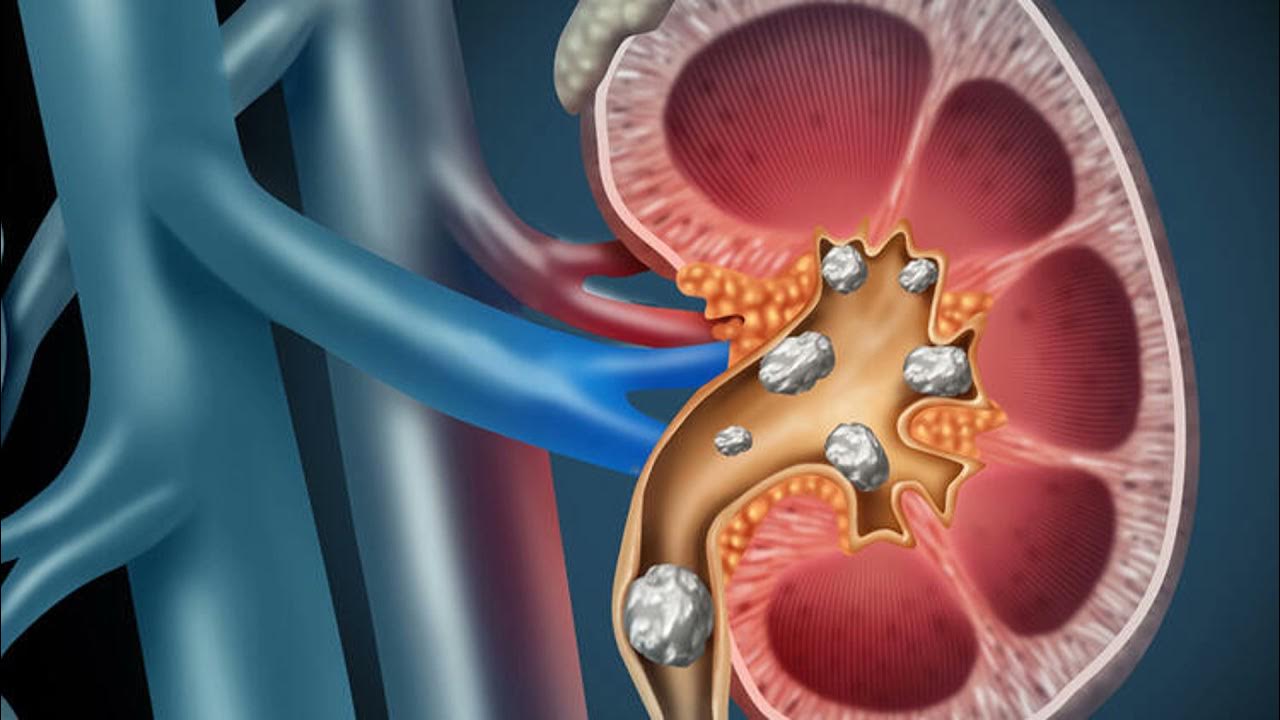

10 erkeğin birinde taş görülüyor

Üroloji Uzmanı Opr. Dr. Osman Gücük, her on kişiden birinde taş oluştuğunu; beslenme, yaşam tarzı ve çevresel etkenlerin hastalığı tetiklediğini kaydetti Ekol Hastanesi’nden Üroloji Uzmanı Opr. Dr. Osman Gücük, böbrek taşının her 10 erkekte birinde, kadınlarda da 30’da 1 oranında görüldüğünü belirtti. Opr. Dr. Gücük, “Yaşamı boyunca bir kez üriner…